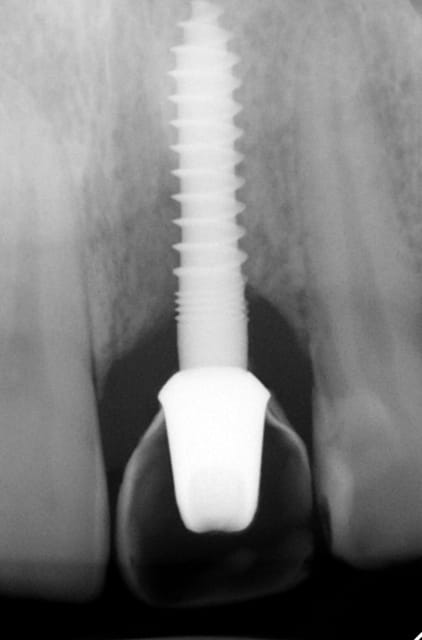

J'ai de tout en boutique..jeune homme 25 ans accident de piscine choc sur la bordure ( fêlure existante..fistule), extraction le jour même, temporisation 4 mois (avec un bout de trombone) Monobloc 16mm 60N, prep cap zircone droit 2/2 provisoire ion, temporisation 3 mois ceramo ceram..

J'ai de tout en boutique..jeune homme 25 ans accident de piscine choc sur la bordure ( fêlure existante..fistule), extraction le jour même, temporisation 4 mois (avec un bout de trombone) Monobloc 16mm 60N, prep cap zircone droit 2/2 provisoire ion, temporisation 3 mois ceramo ceram.. suite des photos :)

Au contraire..si tu regarde attentivement les radios tu veras qu'en quelques mois il y a une néoformation osseuse autour des micros spires. On voit un manque le jour de la pose et plus d'os avec la Procera. Volontairement j'ai pas plus enfoncé l'implant ..Si j'avais ouvert j'aurai bousillé tout le potentiel cicatriciel..Charon l'a démontré depuis longtemps en paro. Aux patient je leur explique que "Ouvrir c'est comme tondre le gazon avec un motoculteur" .

Donc il y maintien et renfort du parodonte.

Si à ça tu rajoutes "l'amitié" de la gencive avec le zircone il n'y a pas de raisons de perdre quoi que ce soit..